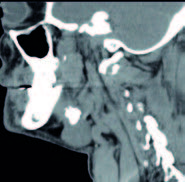

Se presentan unas imágenes de un paciente varón de 55 años, sin alergias conocidas, exfumador desde hace unos pocos años, que consulta por urgencias por inflamación brusca submandibular derecha dolorosa, tiene antecedentes de 5 episodios de submaxilitis derecha por cálculo salivar, desde hace 5 años. En la exploración de la salida sublingual del conducto de Warton se aprecia salida de saliva con supuración. Después de tratamiento antibiótico durante una semana, mejora la inflamación, saliendo saliva clara normal, quedando una hipertrofia de la glándula (figura 4).

La TAC del cuello señala una litiasis submaxilar derecha: ligero aumento del tamaño de la glándula submaxilar derecha observándose en su interior calcificación de 19 x 15 x 15 mm y otras dos pequeñas adyacentes (de 4 y 5 mm respectivamente). No se observan colecciones a nivel de la glándula submaxilar. No se observan otros hallazgos a nivel de laringe o faringe. Sin imágenes ganglionares de tamaño significativo a nivel de las cadenas ganglionares cervicales.